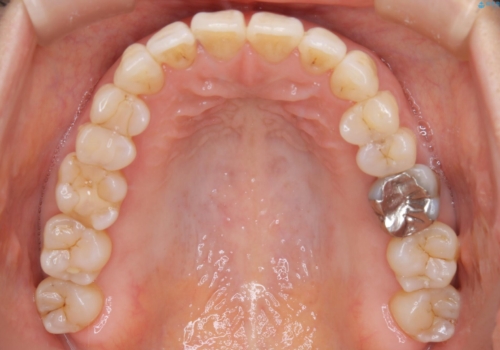

今回のようなケースでは、

抜歯を行うことが困難であり、また歯ぐきと骨が薄いことで

拡大と呼ばれる歯のアーチを広げる処置を行うことも困難でした。

そこで、IPRによるスペースの確保をメインに行いました。

むやみやたらに歯を削る選択をするのではなく、それぞれのスペース確保の手段を比較、検討した上で治療を行います。